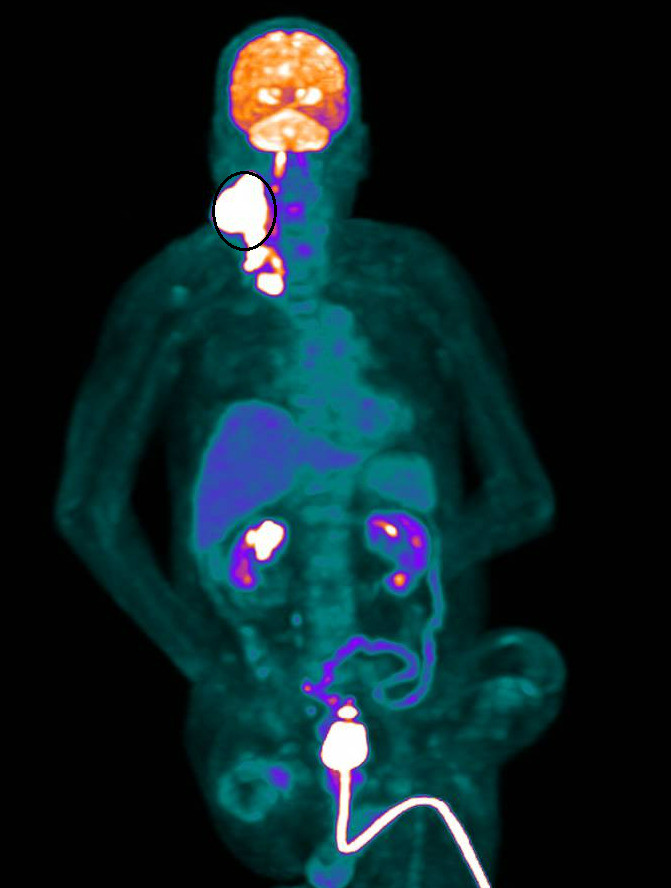

〔記者陳冠備/彰化報導〕真的還可以治!高齡80歲、長期臥床的林姓老翁,四個月前發現右頸部長出一顆10公分的巨大腫瘤,確診為第四期頭頸癌,家屬陷入「治療是否徒增痛苦」的掙扎,最後在衛福部彰化醫院建議下,採用健保給付的放射線治療,經過兩個月療程,原本近10公分的惡性腫瘤竟奇蹟般幾乎完全消失,為高齡癌末患者的治療帶來一道曙光。

張博竣說,林翁隨即展開為期兩個月、共35次的「電療」,途中雖出現疲倦與皮膚反應,但仍順利完成療程。療程結束後,頸部原本明顯突出的10公分腫瘤竟幾乎完全消失,治療效果遠超預期,家屬臉上也露出了久違的笑容。